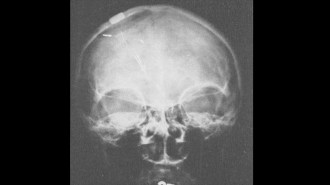

Corbin O'Grady Studio/Science Source

The first detailed image of a living brain is taken by a computerized tomography, or CT, scanner in England. Co-inventor of the technology, Godfrey Hounsfield, is shown.